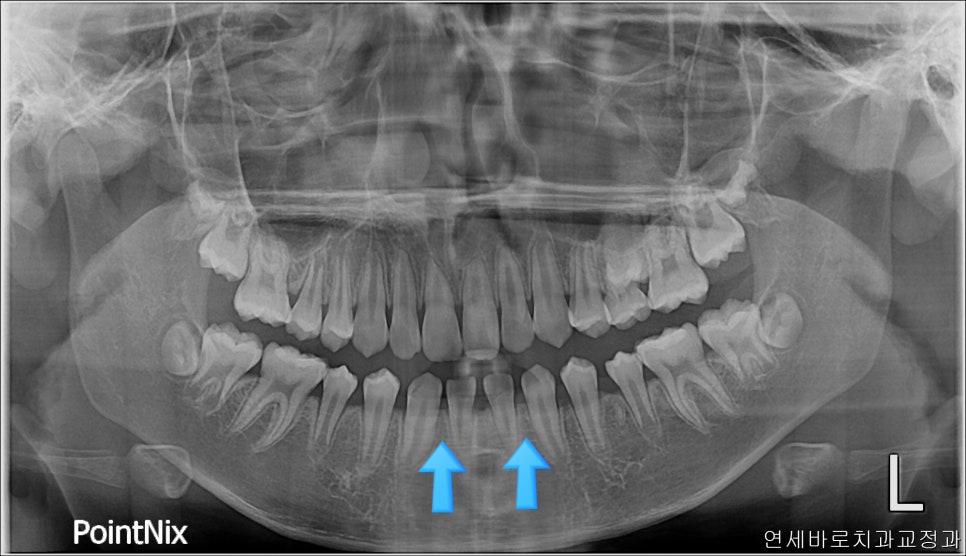

여기 두개의 치아가 더 있어야 했지만

아래쪽 두개가 없을 때 가장 쉬운 방법은 위쪽도 2개의 치아를 없애는 겁니다.

이 친구는 약간의 돌출도 보이고 있었기 때문에 위쪽 치아를 두개 발치했었습니다.

오랜 시간이 지난 뒤 엑스레이에서도 부작용이 관찰되지 않고 잘 유지되고 있네요